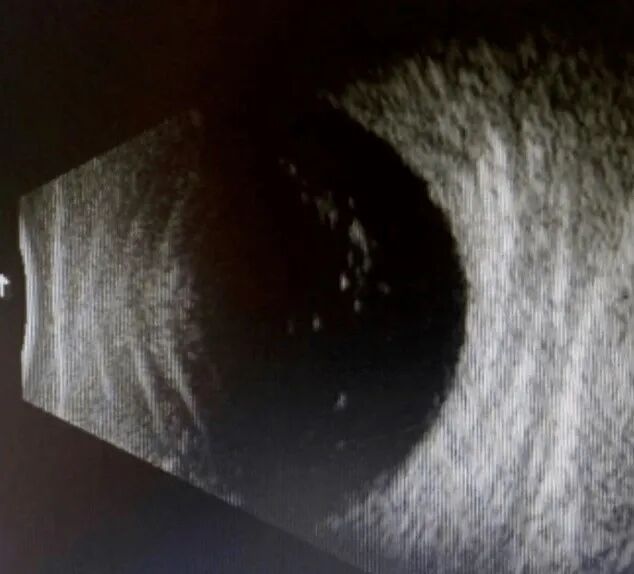

玻璃体混浊